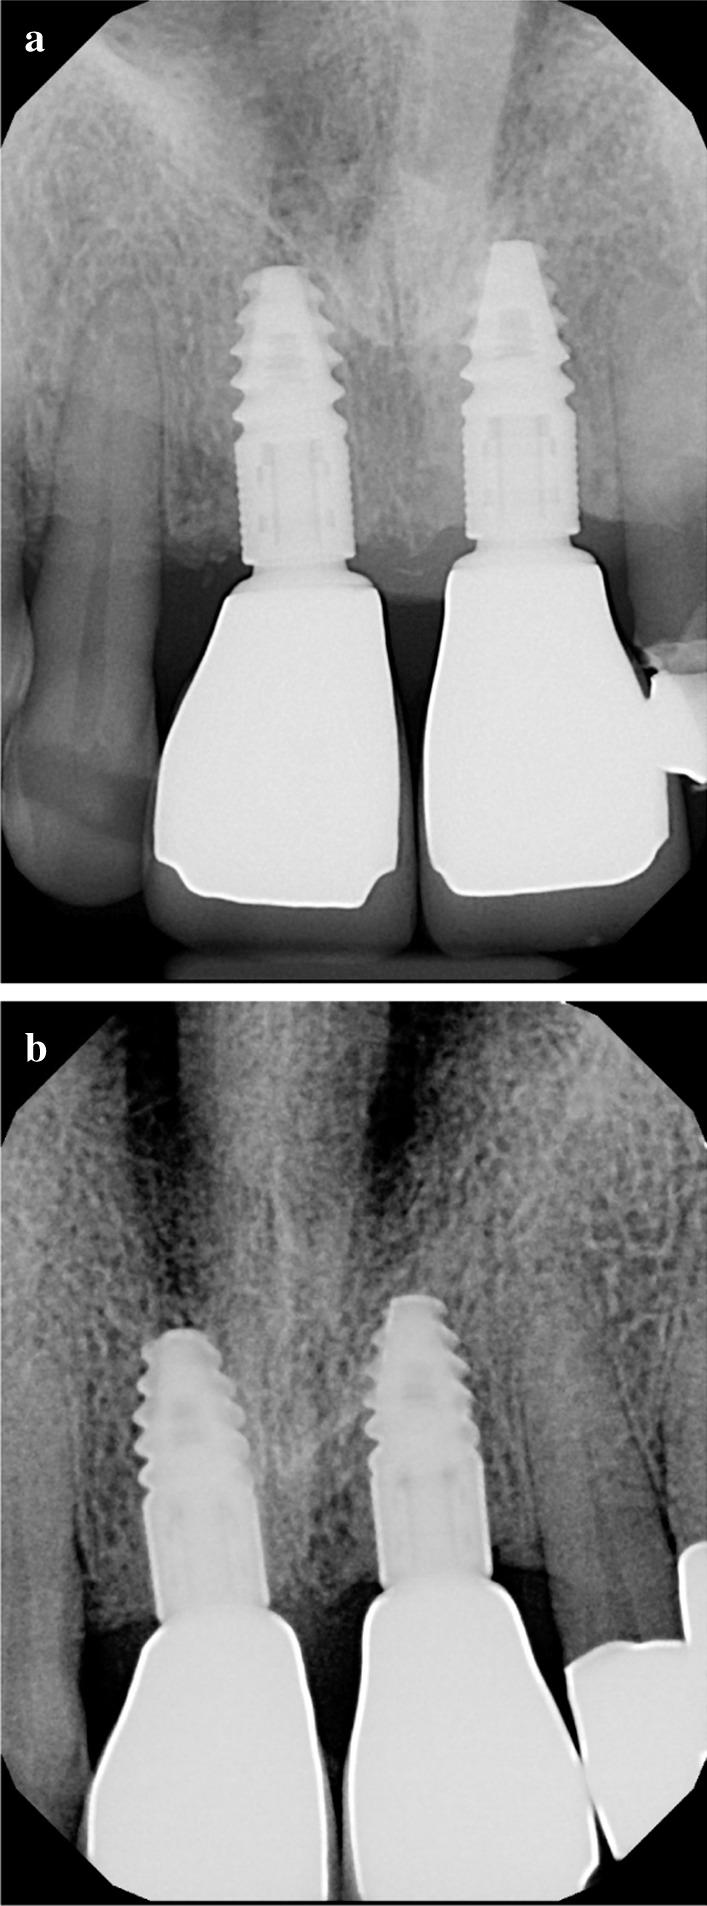

A total of 9 teeth were extracted from 5 patients. The extracted teeth were prepared immediately with the Bonmaker device. The extraction sockets were filled up with ATB powder. Six months after extraction, standardized intraoral x-rays and CBCT scans were performed. Re-entry was performed under local anaesthesia. Core biopsies were harvested for histological analysis and implants were placed.

Horizontal alveolar dimension loss occurred, even though ARP was performed, but the horizontal shrinkage was moderate. Vertical dimensions did not show loss of volume, but increased defect fill. Core biopsies showed ATB particles surrounded by newly formed bone and connective tissue. According to histomorphometric analysis, the harvested samples contained 56% of newly formed bone on average, and only a mean of 7% of non-remodelled ATB material was observed.

从 5 名患者中总共拔出 9 颗牙齿。用 Bonmaker 设备立即对拔出的牙齿进行准备。用 ATB 粉末填充拔牙窝。拔牙后 6 个月,进行标准化的口腔内 X 光和 CBCT 扫描。在局部麻醉下进行再进入。采集核心活检进行组织学分析并植入种植体。

尽管进行了 ARP,但仍发生了水平牙槽骨尺寸损失,但是水平收缩程度适中。垂直尺寸没有出现体积损失,反而增加了缺陷填充。核心活检显示 ATB 颗粒被新形成的骨和结缔组织包围。根据组织形态计量学分析,所采集的样本平均含有 56%的新形成骨,仅观察到平均 7%的未重塑的 ATB 材料。